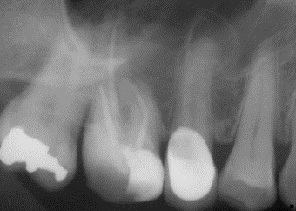

上顎小臼歯と大臼歯の歯根は副鼻腔底に近くにあり、根尖性歯周炎では骨の境界が緩み、細菌が上顎腔に侵入して副鼻腔炎を引き起こす可能性があります。抜歯、顎外科手術、インプラント埋入では、口腔と上顎洞の間に急性的な交通路が残ることがあります。その結果、いわゆる口腔前庭部に口腔上顎洞瘻を形成し、そこから膿が排出され、それが副鼻腔への微生物の侵入点となり、細菌の定着や感染につながる可能性があります(画像2a、2b)。

- 小臼歯/大臼歯領域の歯根尖/歯周領域における放射線透過性(画像3a、画像3b)